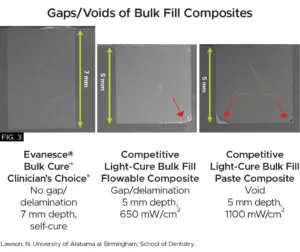

- Bio-Adaptive™ Restorative Performance: The flow characteristics of Evanesce Bulk Cure ensure gap-free margins with all bonding techniques, promoting optimal sealing of both dentin and enamel to enhance marginal integrity, minimizing the risk of microleakage. (FIG. 3) Evanesce Bulk Cure will easily adapt to irregular line angles or preparation variables. Both placement and shrinkage voids are consistently prevented at the proximal box, a common challenge with all light-cure composites.

- Unlimited Depth of Cure and Low Shrinkage Stress: Dual-cure Evanesce Bulk Cure provides an unlimited depth of cure, even when light access is restricted. Its low polymerization shrinkage stress helps to prevent post-operative sensitivity, and gap formation.

Once the ring and sectional matrix are removed, additional Evanesce Bulk Cure composite was used to restore the remaining Class I preparation. Due to the “bio-adaptive” nature of Evanesce Bulk Cure, it allows for the bulk filling of essentially the entire occlusal preparation in one large increment of composite with virtually zero voids on the margins or pulpal floor. In addition, Evanesce Bulk Cure is a dual-cure composite which provides an unlimited depth of cure, even when light access is diminished due to deep restorations. When allowed to self-cure for 30-60 seconds after placement, its low polymerization shrinkage stress also helps to prevent post-operative sensitivity. (FIG.10)